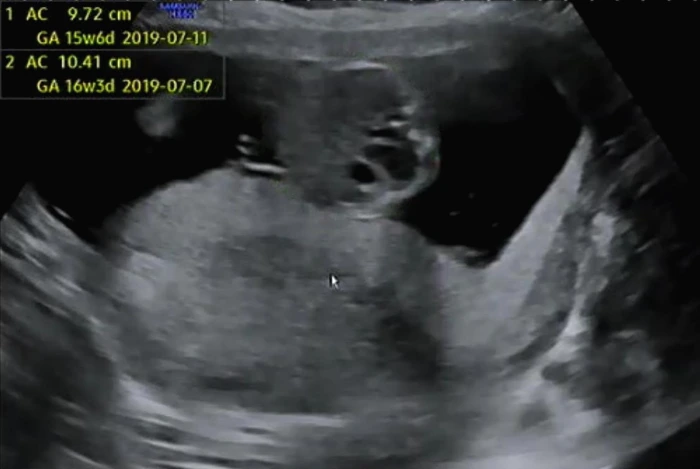

BPD(태아의 머리둘레)와 AC(태아의 복부둘레)를 측정하고 이후 심장소리를 확인했다. BPD와 AC로 이용하여 주수에 맞게 잘 자라고 있는지 확인했다. 아기는 여전히 잘 자라고 있다고 일정하게 심장소리를 들려주며 초음파 상으로 열심히 움직이고 있었다.